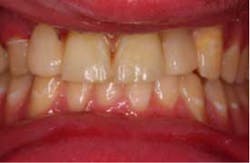

The restorations were etched with phosphoric acid, cleaned with Ivoclean (*), and bonded with universal bond (*). The preparations were isolated (isolation was very difficult in the area of No. 7 due to surgery the day before), etched, bonded, and the restorations were cemented. Special attention was paid to the occlusion on the FPDs, and all occlusal contact was removed from the connector area. Also, all anterior guidance was removed from the FPDs. The opposing dentition was reshaped to gain as ideal of a contact on the restorations as possible. The patient returned one prior to his leaving to verify his occlusion and post-treatment photographs. At this time, the patient was instructed about hygiene for the restoration and how to carefully function with the restorations. He seemed to be pleased with the functionality and esthetics of the restorations.